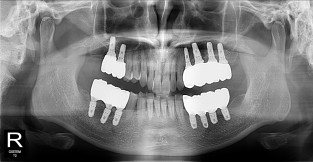

• 2

전체어금니

치료기간 : 2021-11-08 ~ 2022-12-22

1. 상기 x-ray 이미지 모두 동일한 해당 의료기관에서 진료한 환자입니다.

2. 상기 x-ray 이미지 모두 동일 인물의 것입니다.

3. 치료 전 이미지는 2021-11-08에 촬영했으며, 치료 후 이미지는 2022-12-22에 촬영하였습니다.

4. 상기 x-ray 이미지 모두 동일 조건에서 환자분의 동의를 받아촬영되었습니다.

* 임플란트 시술은 환자분의 상태(고혈압, 당뇨 등)에 따라 부작용이 있을 수 있으니, 반드시 전문의와 상담이 필요합니다.

* 임플란트 수술 부작용

: 수술 후 출혈, 교합, 통증, 붓기, 염증 등의 문제점이 발생할 수 있습니다.)

* 본 이미지들은 의료광고법을 준수하여 게시하였으며, <의료법 제 56조 제2항 제7호>에 의거하여 개개인의 신체 상태와 질병 진행도 등 여러 요인에 따라 치료 효과가 상이하기에 진료계획 또한 달라질 수 있음을 고지해드립니다.